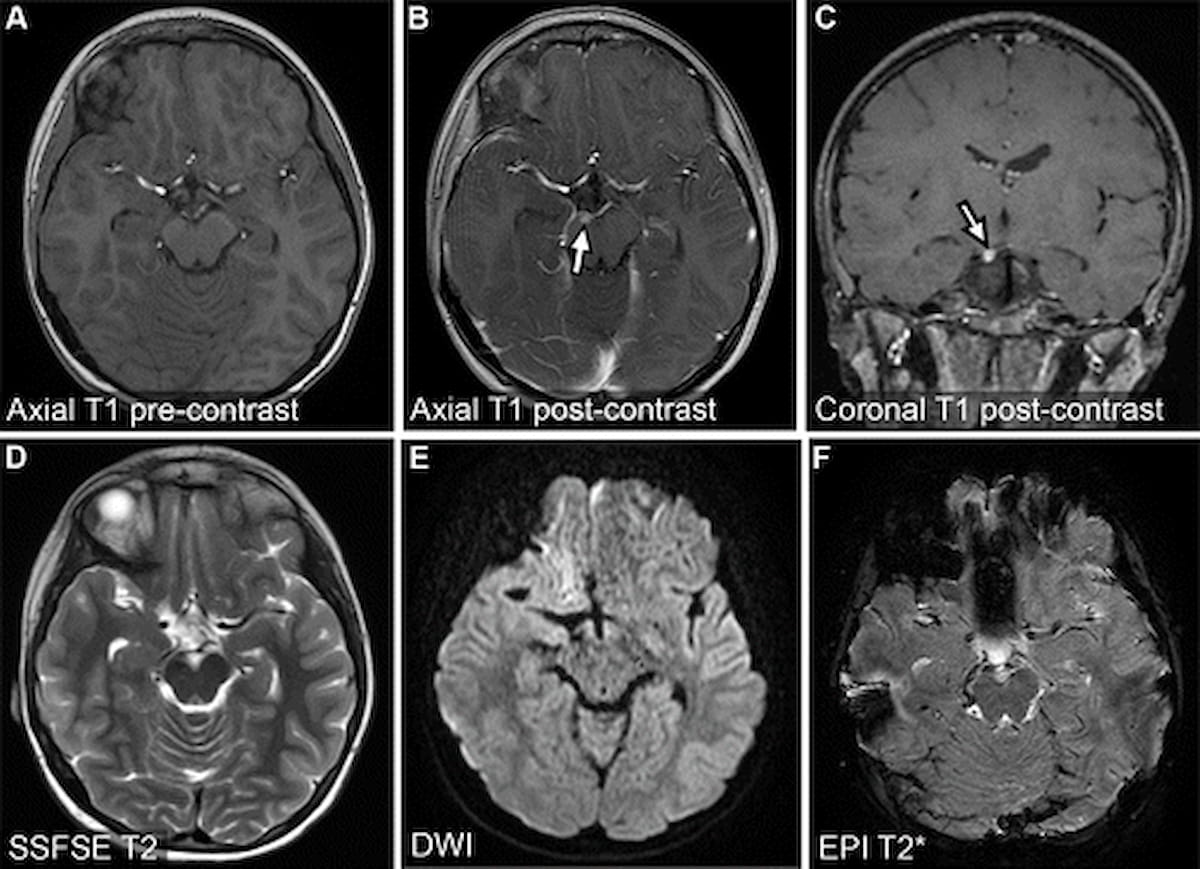

In a recently published review, radiology researchers from the University of Wisconsin discussed the potential and key considerations for applying accelerated magnetic resonance imaging (MRI) protocols in the assessment of emergent and urgent conditions.